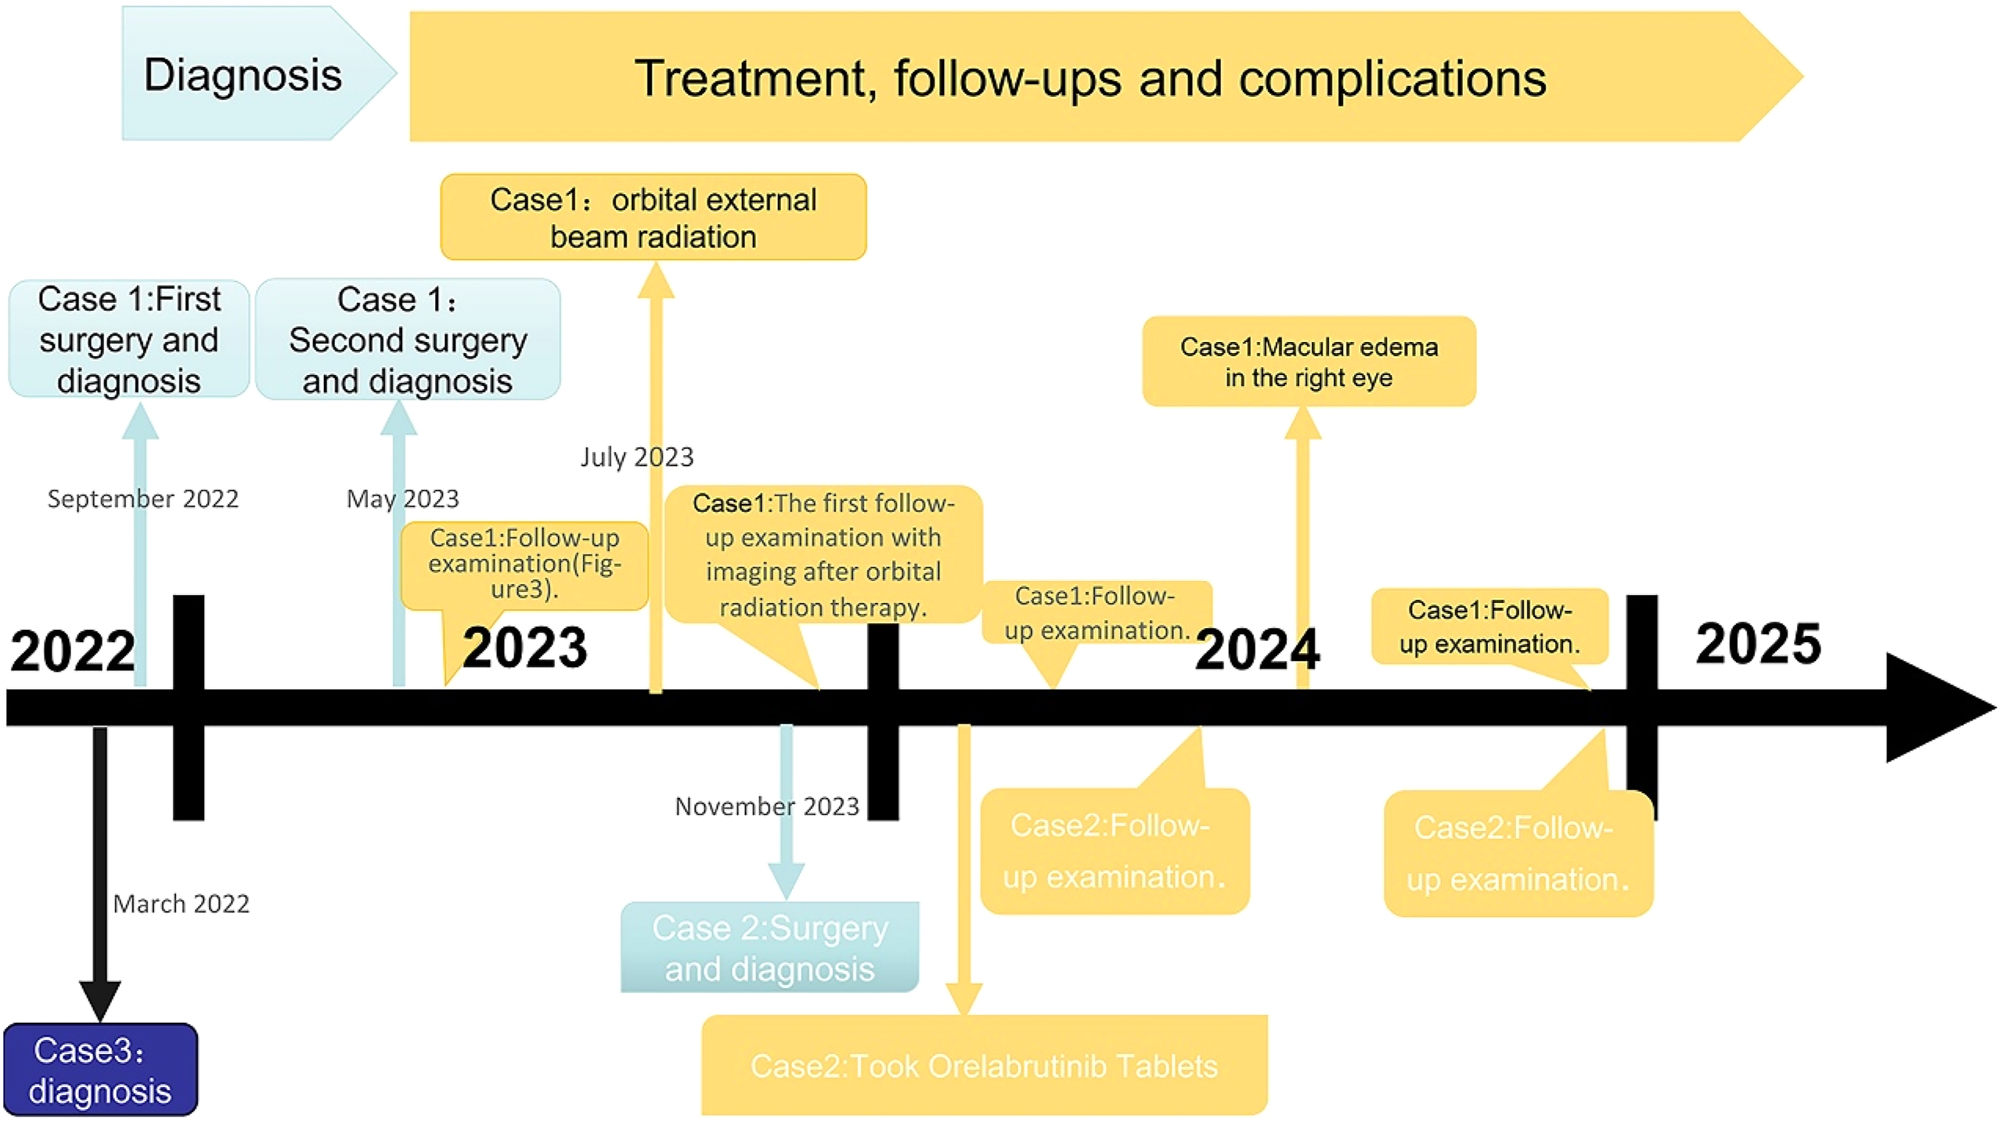

Three cases of orbital MALT lymphoma with localized amyloidosis recorded in the databases of the Ophthalmology and Pathology Departments of West China Hospital of Sichuan University from 2022 to 2025 were reviewed (Figure 1). This study was conducted considering ethical responsibilities according to the World Medical Association and the Declaration of Helsinki and was approved by the Ethics Committee of West China Hospital, Sichuan University (NO. 2025-494). The handwritten informed consent was obtained from the patients.

The timelines for three patients include the process of diagnosis, treatment, and follow-ups.